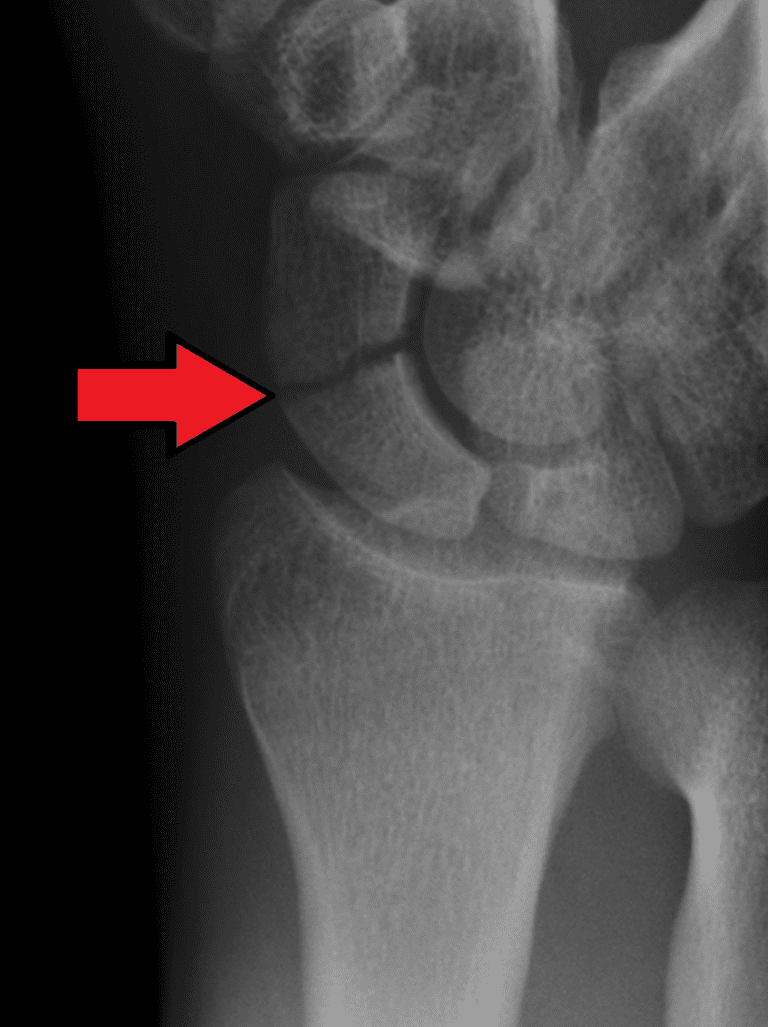

Scaphoid fracture Image